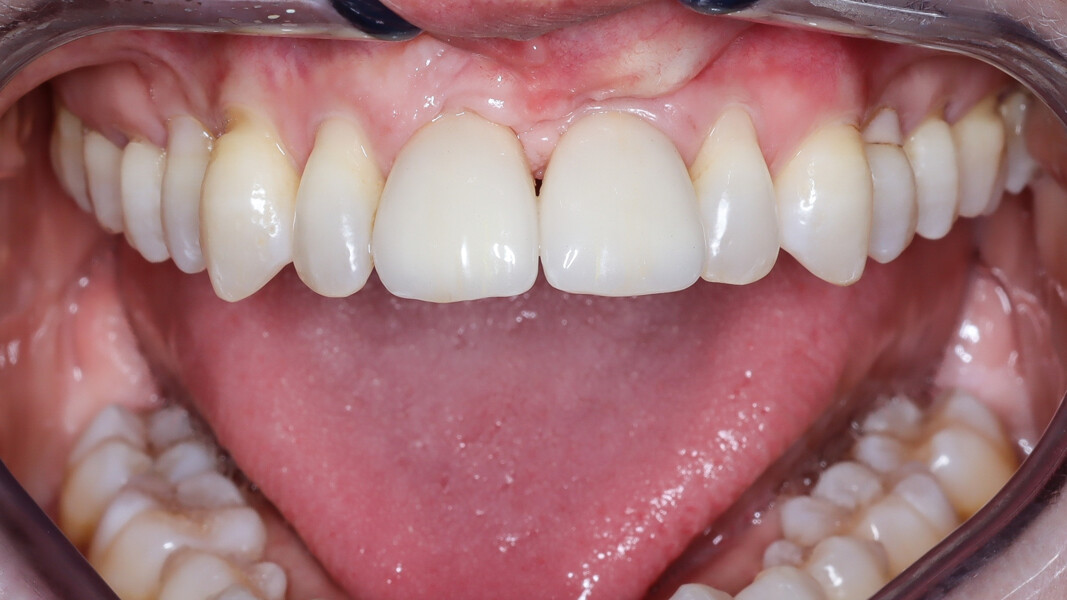

Une patiente de 49 ans nous a été adressée par l’un de nos confrères pour le remplacement de ses quatre incisives maxillaires (Fig. 23). Dans un contexte parodontal avancé, ses incisives centrales présentent une mobilité terminale (classe IV) elle n’ose plus les brosser de peur de les perdre lors de la manoeuvre. La patiente ne présente pas de problèmes de santé particuliers.

À l’examen, on observe une mobilité des quatre incisives maxillaires, une insuffisance osseuse verticale et horizontale, associées notamment au niveau de 11 et 21, la présence de plaque, de tartre et d’inflammation gingivale, surtout au niveau du bloc antérieur maxillaire. On note également la présence d’une dent de sagesse (dent 18) perdue (Figs. 24–26).